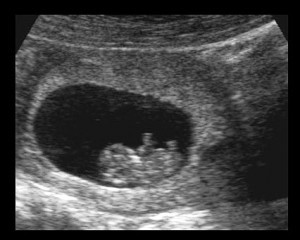

На трансвагинальном УЗИ уже можно увидеть вашего малыша и как бьется его сердечко.